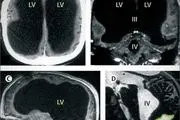

• جشن کرم‌ها داخل مغز این مرد! + عکس

جشن کرم‌ها داخل مغز این مرد! + عکس

مرد روستایی به دلیل حالت تهوع شدید به بیمارستان مراجعه کرد ، مشکل در بررسی های اولیه پزشک مشکوک به تومور بود اما علت اصلی زندگی کردن بیش از 30 تخم کرم زنده داخل مغز بیمار بود.

۲۵ مرداد ۱۴۰۰